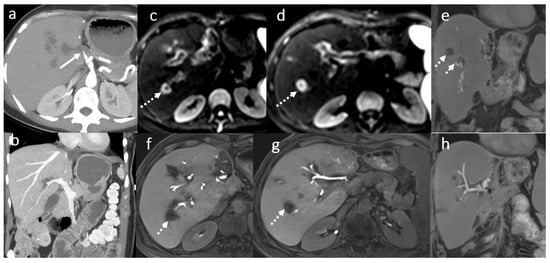

3.5. Biloma and Bile Leaks

3.6. Secondary Cholangitis

3.7. BT Lithiasis

3.8. Primary Sclerosing Cholangitis